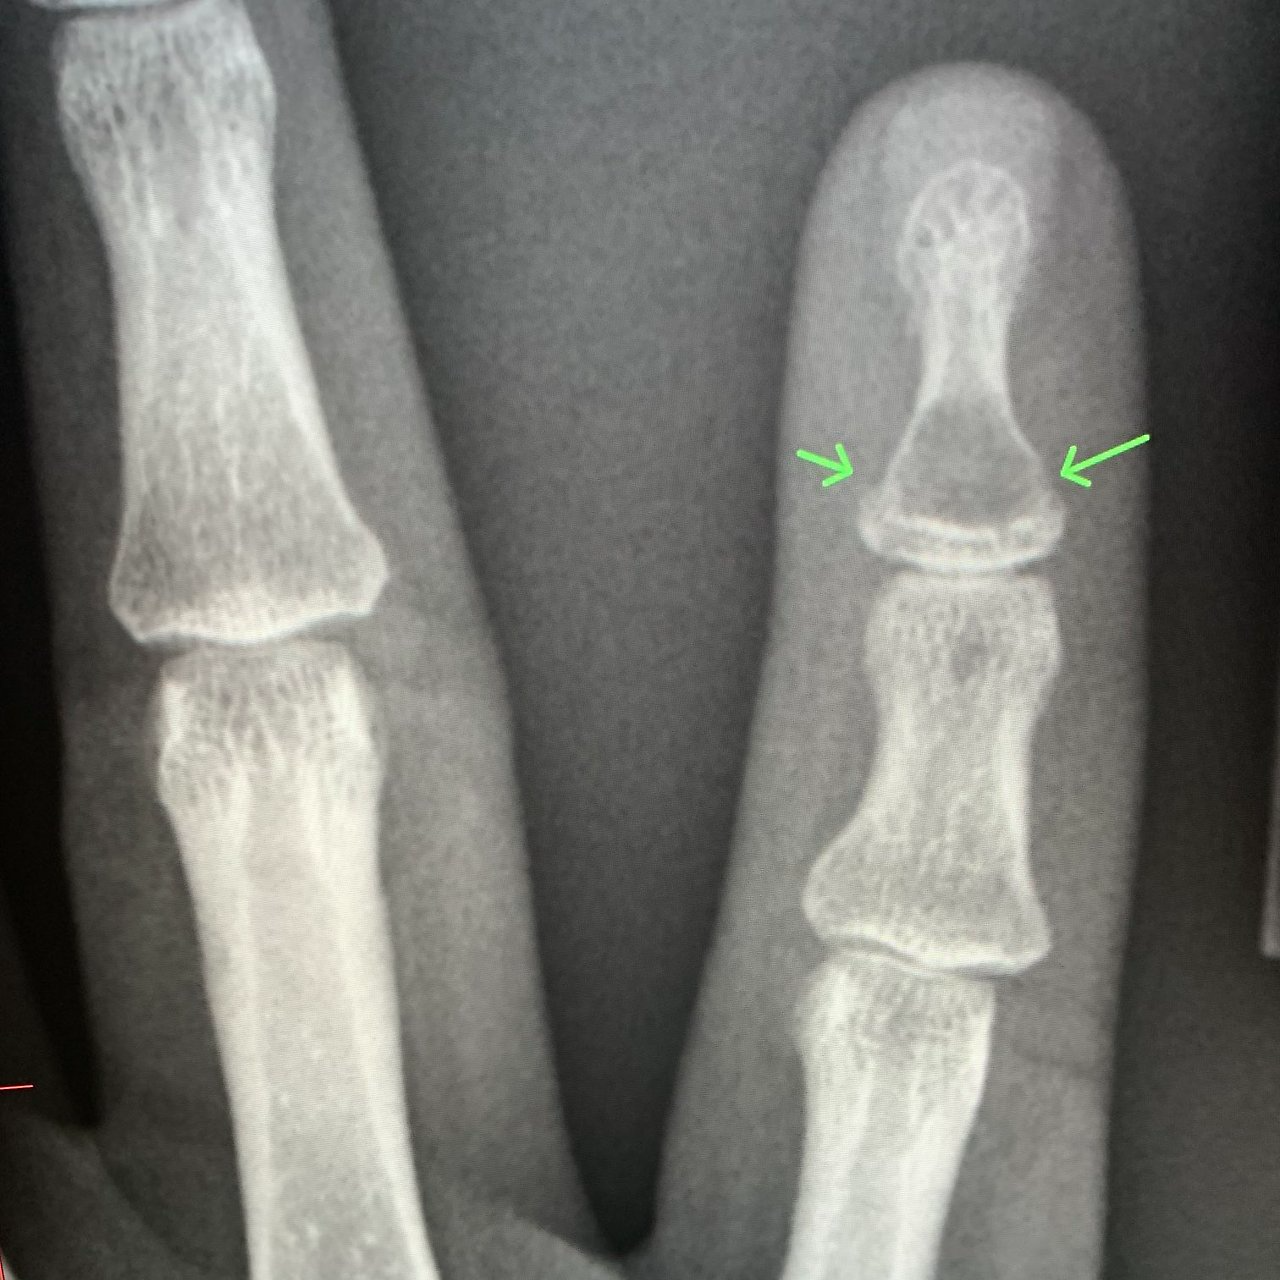

발가락 골절 증상·진단 포인트

- 국소 붓기·홍반·멍

- 걸을 때 날카로운 통증 또는 불안정감

- X-ray 2 방향 촬영이 1차 진단 표준

- 모호할 경우 CT/MRI 추가